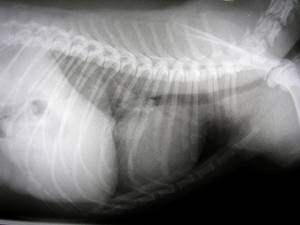

Das Röntgen ermöglicht eine relativ einfache Untersuchung des Herzens, dementsprechend „einfach“ fällt auch meist der Befund „Herzvergrößerung“ aus, ohne eine zuverlässige Aussage über die eigentlichen inneren Ursachen zuzulassen. Dennoch ist eine Röntgenuntersuchung von unschätzbarem Wert, da sich auf den schwarz-weiß Bildern die Ausmaße der begleitenden Symptome abzeichnen. So ist es beispielsweise möglich, ein sog. Lungen-Ödem (= Wasser in der Lunge aufgrund der Herzschwäche) zuverlässig zu erkennen und entsprechend zu behandeln. |

Röntgen |